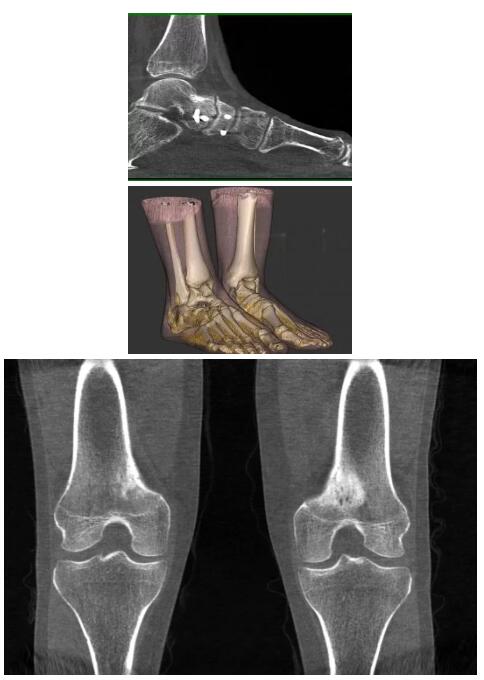

另外一款被稱為世界上最小的CT,它的重量僅300磅,不僅能夠掃查足部,還可以檢查膝蓋和上肢等。

與上面介紹的CT一樣,它同樣具有輻射低、占地空間?。?3*36)的特點,隨開隨用(支持直接接入墻上的插座)。

這款CT使用非常方便,通過上下移動保持與患者的手臂或者雙腿齊平,掃描快速,僅需要30秒左右就可以完成掃查。

以上介紹的CT均來自國外同一家公司,這些CT均配置了可視化軟件,可以進行切片、3D重建以及大型CT附帶的所有典型的操作功能。

當(dāng)然,這類充滿想象力的CT,國內(nèi)也有生產(chǎn)廠家在研究,比如賽諾威盛研發(fā)的InsitumCT Zero,可以很好的適應(yīng)特殊的臨床應(yīng)用場景,超大孔徑多種自由度組合,可實現(xiàn)水平和垂直等多種掃描模式。

以下是這些“特立獨行”的CT所拍出來的圖像: